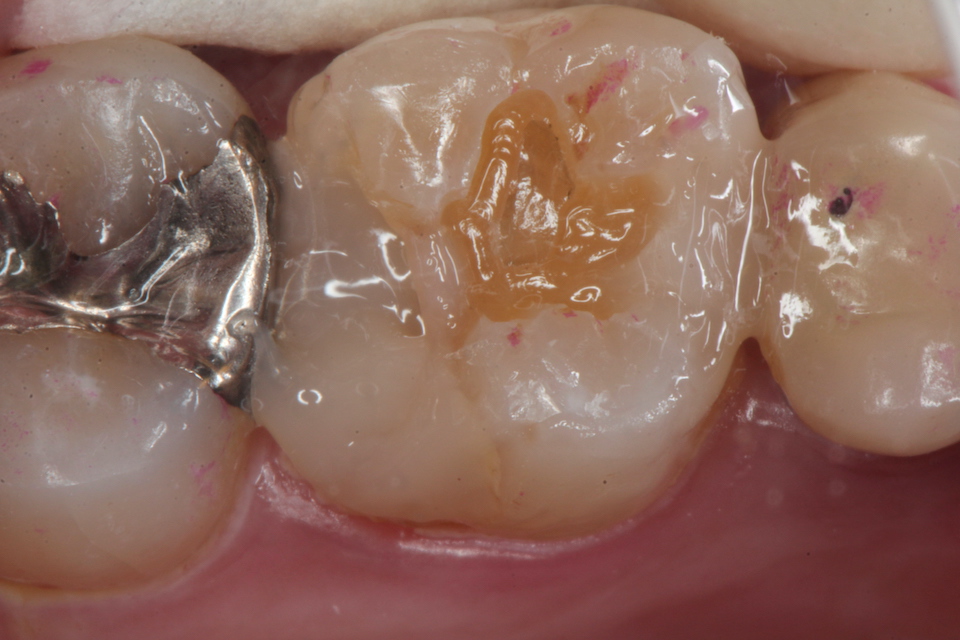

残根上のCR(ダイレクトボンディング)8 2025.11.12

ブリッジ脱離で2次カリエス+Perでグラグ… 2025.11.01

ブリッジ脱離で2次カリエス+Perでグラグ… 2025.10.31